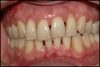

Gencive très inflammatoire

Déchaussement = migration des gencives